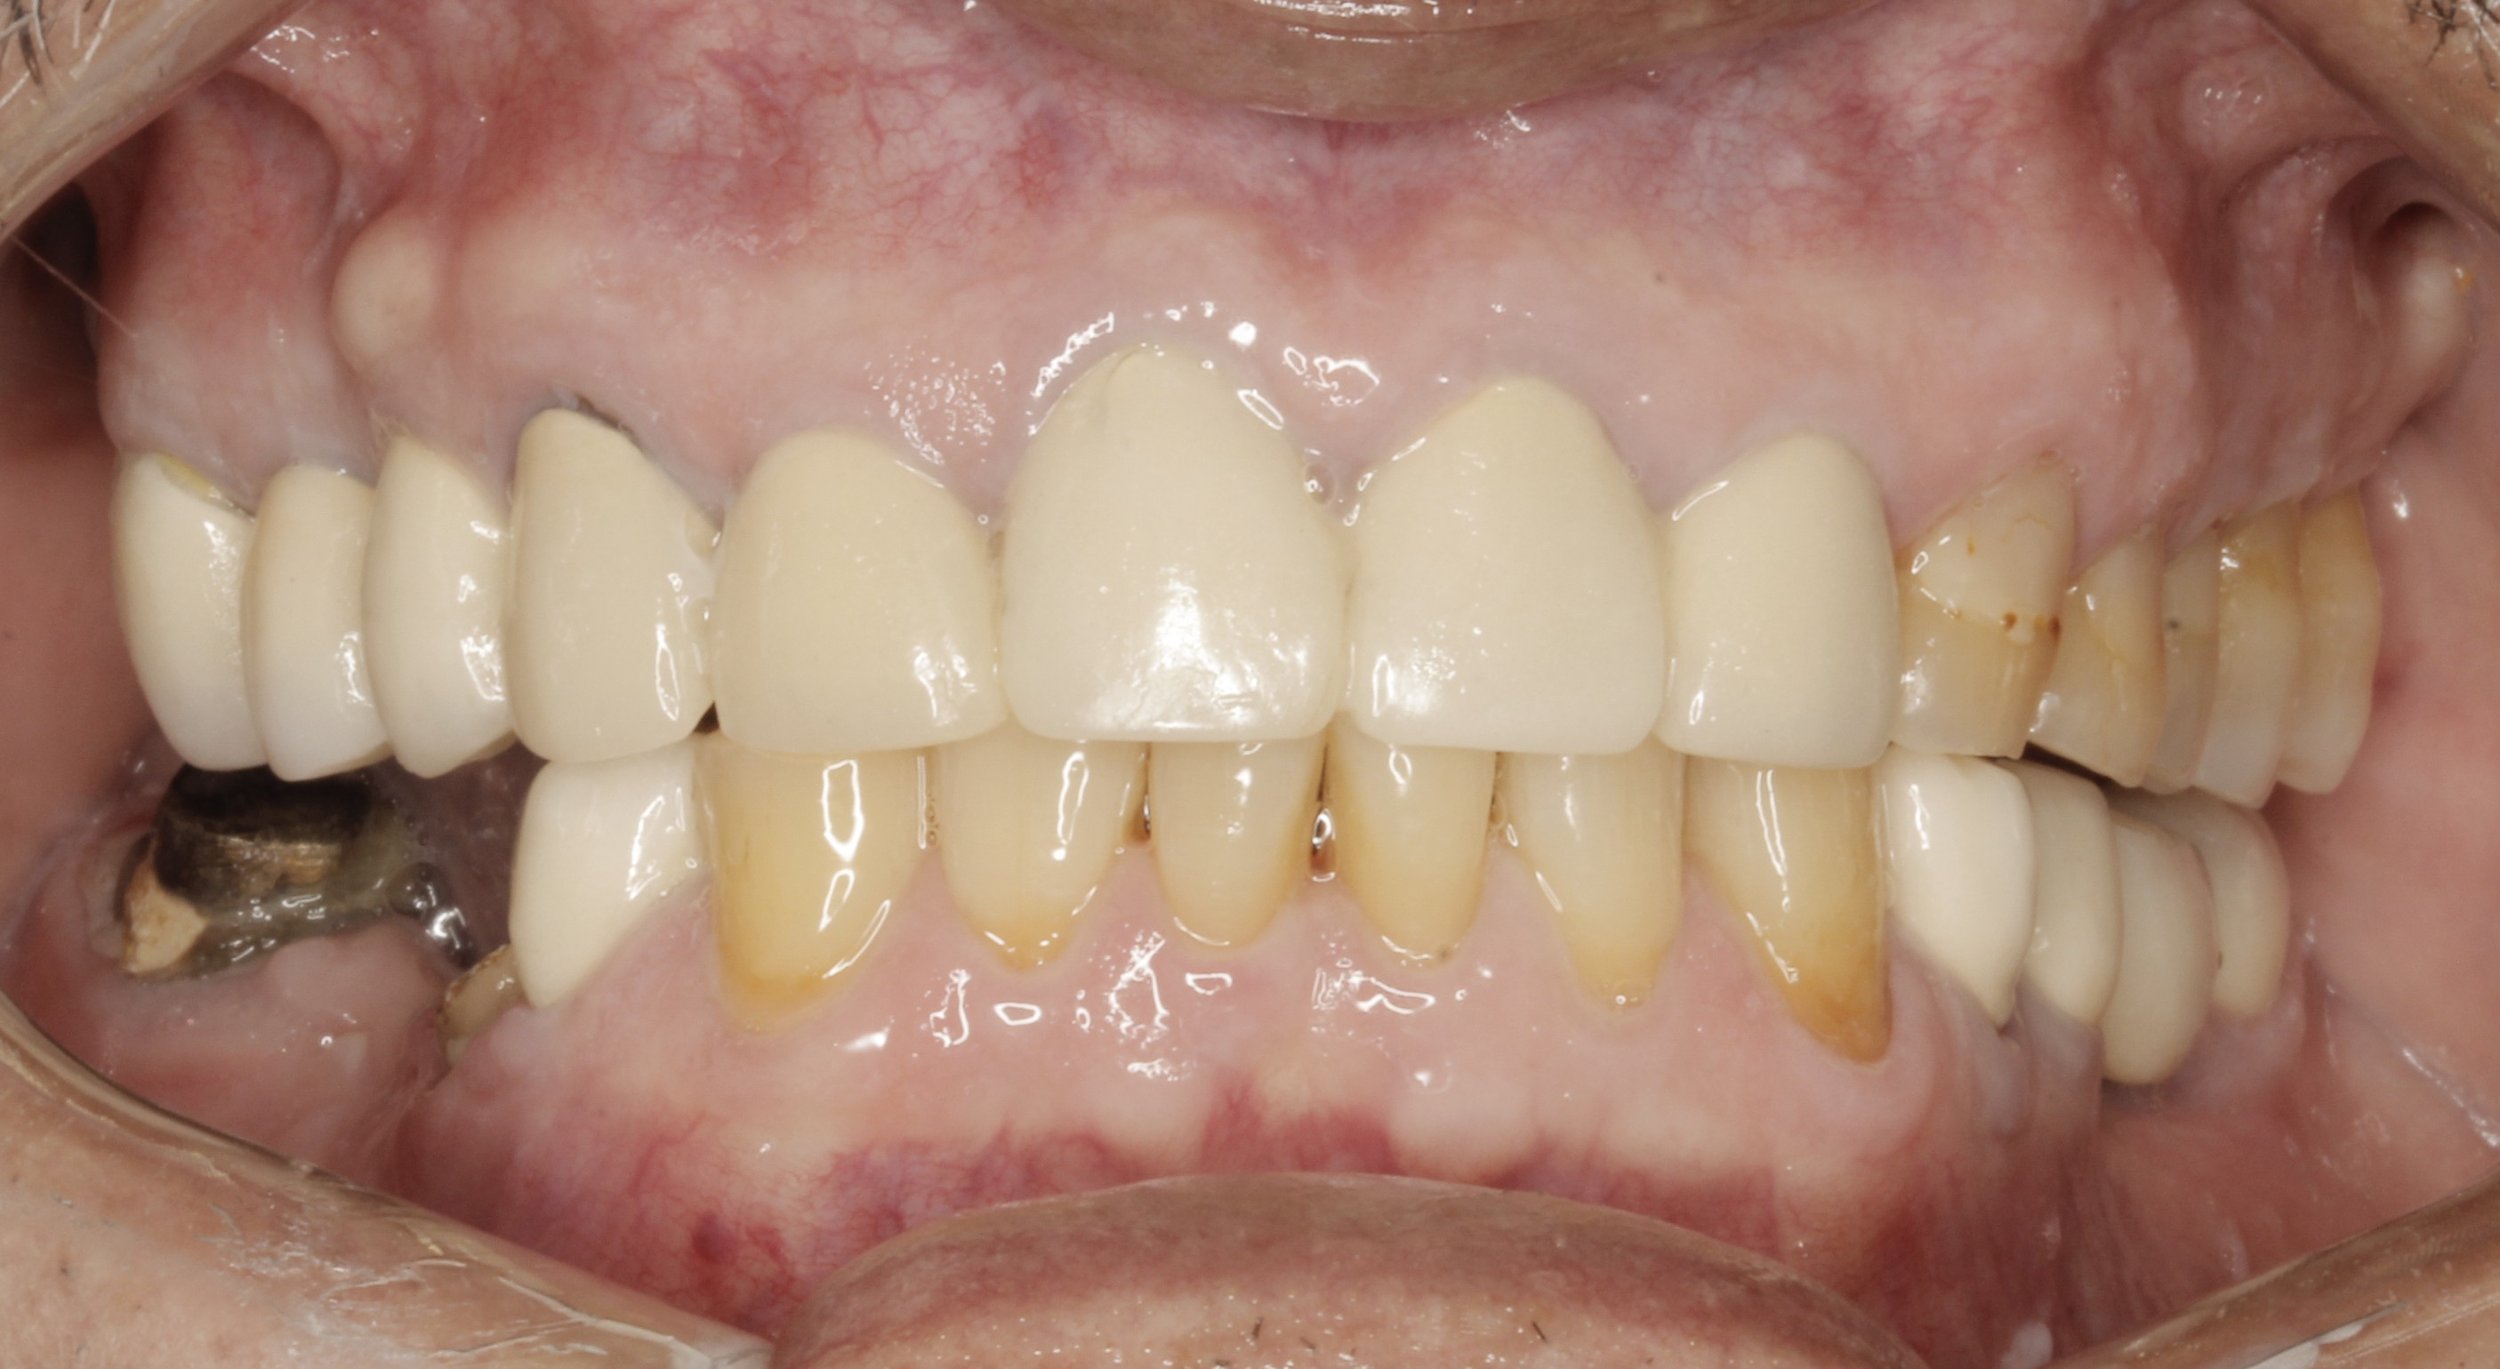

Fotografías iniciales

Antes

Fractura de puente fijo

Estudios previos